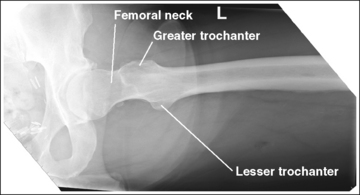

See Figure 6-64 and Box 6-13.